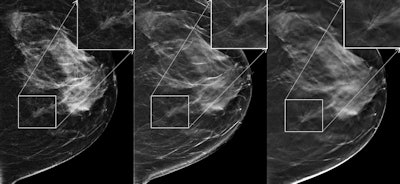

Mediolateral oblique images in 61-year-old woman with 12-mm invasive lobular carcinoma in the right breast. Left: FFDM image; middle: current synthesized 2D image; right: DBT image. The region of interest is magnified for each image. Reader scores for the study were 1 for FFDM, 3 for FFDM plus DBT, and 4 for synthesized 2D images plus DBT. This case was from study period 2.Skaane and colleagues also found comparable cancer detection rates between the two combinations: